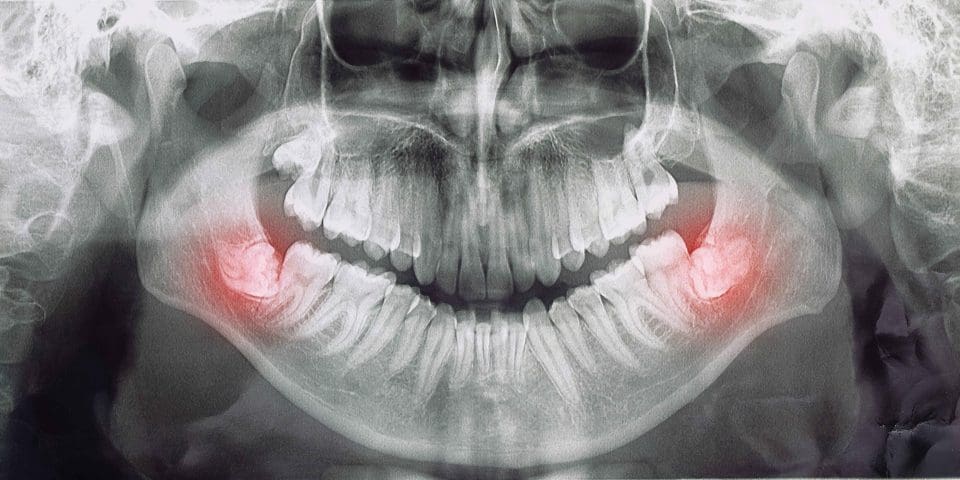

20lik diş çekimi öncesi dişin durumu detaylı bir şekilde değerlendirilmelidir. 16 yaşından itibaren yirmi yaş dişlerinin düzenli takibi önerilmektedir. Yirmilik diş çekimi normal bir diş çekimi kadar kolay olabileceği gibi bazen cerrahi müdahaleler de gerekebilir. Dişin durumu öncelikle panoramik röntgen veya üç boyutlu dental tomografiye ek olarak klinik muayene ile belirlenmelidir. Çene yapısına uygun olan ve rahatlıkla ağız içerisine sürmüş dişlerin çekimine gerek olmayabilir. Ancak bazen 20 yaş dişleri yanlış açıda çıkabilir veya hiç belirti vermeden diş eti ile örtülü kalarak dışarıdan görünmeyebilir. Düzenli diş hekimi muayenesi ile dişin gelişimi ve sürme yönü takip edilebilir. Takip altındaki yirmilik dişler çene kemiği veya komşu dişler üzerinde herhangi bir olumsuzluk yaratmadan gerekli müdahaleler yapılabilir.

Yirmi yaş dişler, ağızda ağrı, şişlik veya diğer semptomlar gösteren hastalarımızda, diş röntgeni çekerek teşhis edilir. Bu röntgen, dişlerin kökleri, kemik yapıları, açıları ve gömülü olan dişleri gösterir. Dışarıdan görünmeyen, yatay çıkmış ya da yarı gömülü dişler röntgende tespit edilir. Doktorlarımız, diş röntgenini inceleyerek normal diş çekimi ile mi yoksa cerrahi operasyonla mı alınması gerektiğine karar verirler.

Bu dişlerin nasıl çekileceğine karar vermek için öncelikle dişin röntgeni çekilir. Düzgün çıkan ama çürük veya ağızda sıkışıklık nedeniyle çekilmesi gereken dişler, diğer dişlerin çekimi gibi basit bir işlemle çekilebilir. Ancak, sorunlu dişlerin büyük çoğunluğu cerrahi bir işlem olan diş ameliyatı ile çekilir. Daha ileri durumlarda ise farklı diş düzeltme yöntemleri de düşünülmelidir.

20 yaş dişleri, normal dişlerin çekiminden daha zor ve karmaşık olabilirler. Gömülü veya yarı gömülü dişlerin çekimi genellikle cerrahi operasyon gerektirirken, normal dişlerin çekimi ameliyatsız yapılabilir. Akıl dişlerinin konumuna, büyüklüğüne ve kapladığı dokunun kalınlığına bağlı olarak, diş çekiminin zorluğu farklılık gösterir. Bu nedenle, diş röntgeni çekildikten sonra diş hekimleri, dişin çekim yöntemini belirlerler. Ancak, yirmilik dişlerin konumu ve büyüklüğü normale uygun ise, çekim işlemi normal diş çekimi ile aynı şekilde gerçekleştirilir.